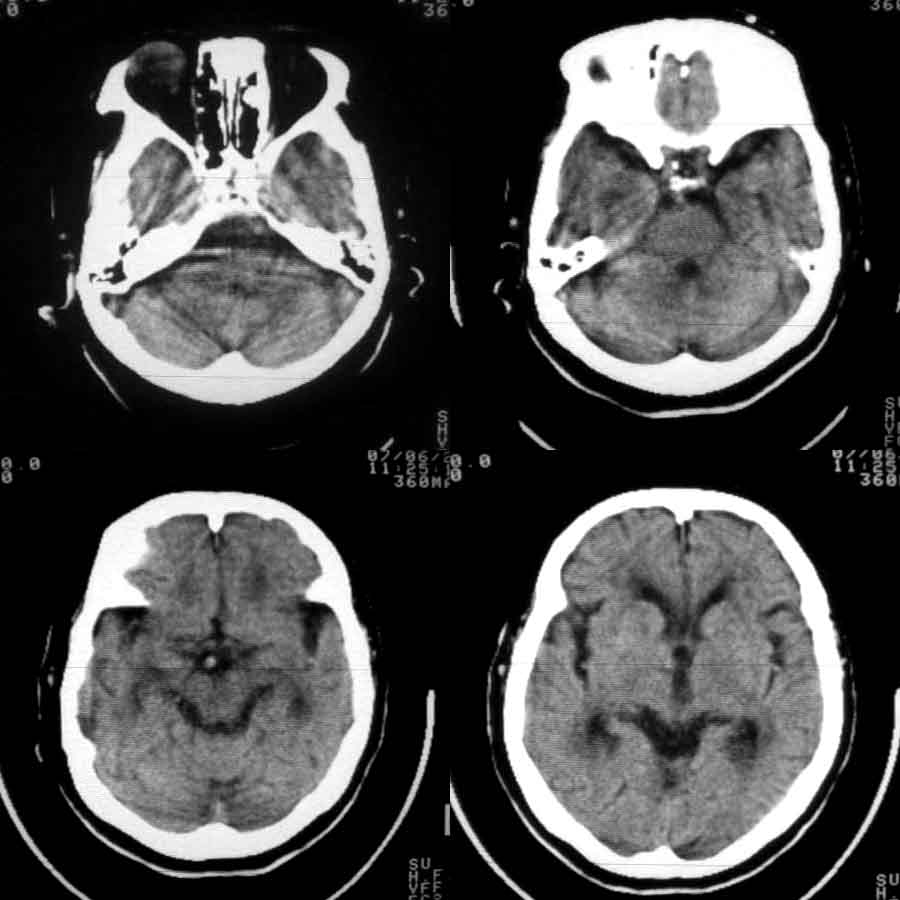

标题: CT8860:陈旧性脑出血 [打印本页]

标题: CT8860:陈旧性脑出血

女81岁,头晕、流延。

06年6月11日

06年6月24日

07年6月28日

1:支持左侧丘脑脑出血吸收演变

2:皮层下电脑硬化性闹病。

1、左丘脑区脑出血吸收期改变。

2、皮层下动脉硬化性脑病。

考虑:1、左丘脑区脑出血吸收期改变。

2、皮层下动脉硬化性脑病伴脑萎缩。